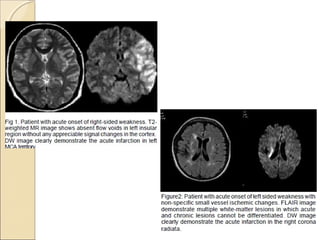

DWI & ADCDWI & ADC

Diffusion-weighted MRIDiffusion-weighted MRI

 Diffusion-weighted MRI is a example of endogenous contrast,

using the motion of protons to produce signal changes

 DWI images is obtained by applying pairs of opposing and

balanced magnetic field gradients (but of differing durations

and amplitudes) around a spin-echo refocusing pulse of a T2

weighted sequence.

 Stationary water molecules are unaffected by the paired

gradients, and thus retain their signal.

 Non stationary water molecules acquire phase information

from the first gradient, but are not re phased by the second

gradient, leading to an overall loss of the MR signal

 The normal motion of water molecules within living tissues is random

(brownian motion).

 In acute stroke, there is an alteration of homeostasis

 Acute stroke causes excess intracellular water accumulation, or

cytotoxic edema, with an overall decreased rate of water molecular

diffusion within the affected tissue.

 Reduction of extracellular space

 Tissues with a higher rate of diffusion undergo a greater loss of signal

in a given period of time than do tissues with a lower diffusion rate.

 Therefore, areas of cytotoxic edema, in which the motion of water

molecules is restricted, appear brighter on diffusion-weighted images

because of lesser signal losses

 Restriction of DWI is not specific for stroke

The primary application of DW MR

imaging has been in brain imaging, mainly

because of its exquisite sensitivity to early

detection of ischemic stroke

The increased sensitivity of diffusion-

weighted MRI in detecting acute ischemia

is thought to be the result of the water

shift intracellularly restricting motion of

water protons (cytotoxic edema)

whereas the conventional T2 weighted

images show signal alteration mostly as a

result of vasogenic edema

Core of infarct = irreversible damage

Surrounding ischemic area  may be

salvaged

DWI: open a window of opportunity

during which Tt is beneficial

Regions of high mobility “rapid diffusion”

 dark

Regions of low mobility “slow diffusion”

 bright